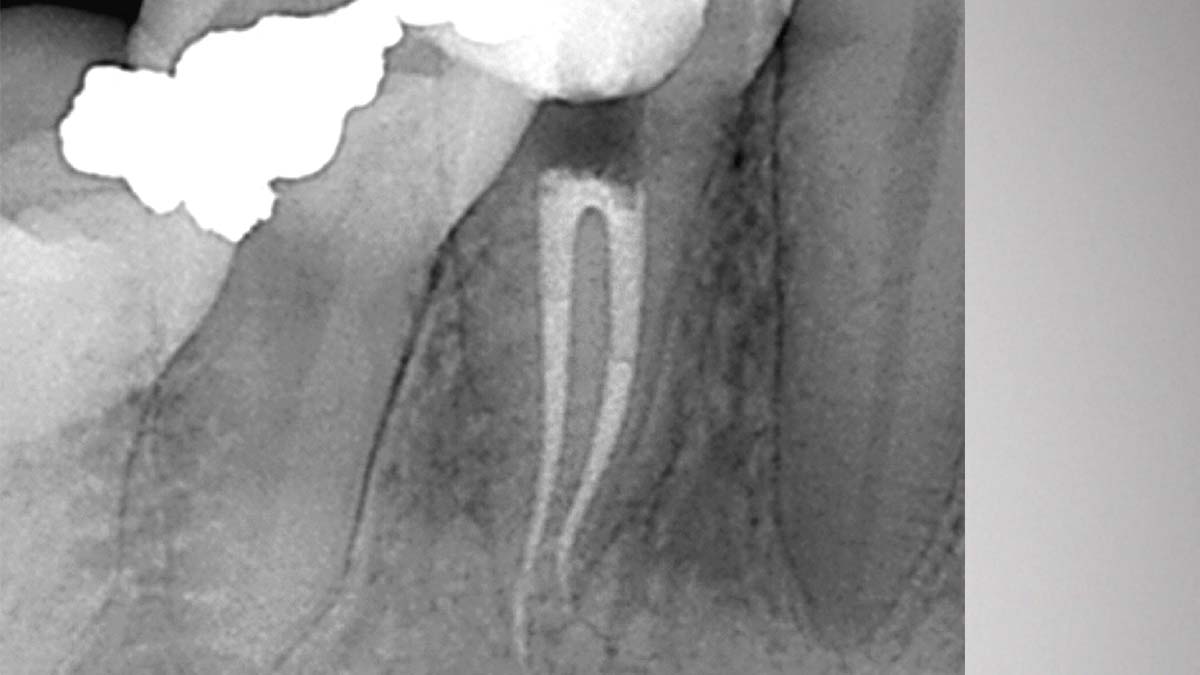

À droite : Gutta-Smart et Conform Fit utilisent la même gutta-percha avancée pour une cohérence radiographique.

Avec l’aimable autorisation du Dr Nathaniel Behrents, Fayetteville, AR